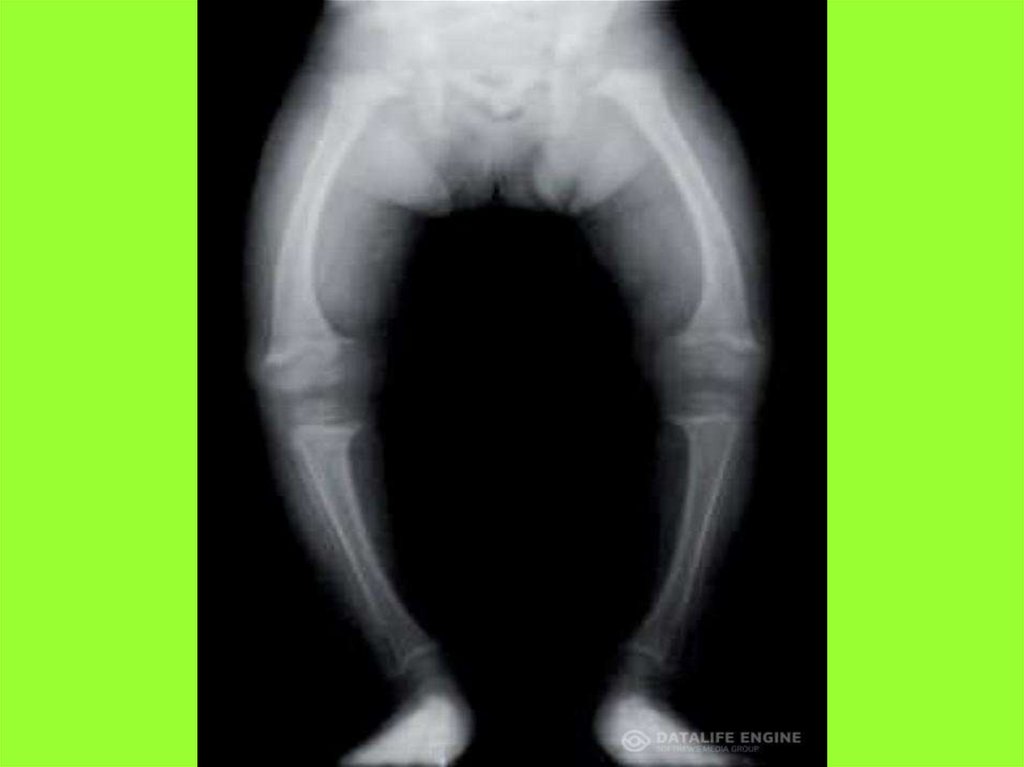

1. РАХИТ

Впервые рахит описал всем

известный учёный, медик Гален.

В переводе с греческого языка

rahis – обозначает позвоночный

столб.